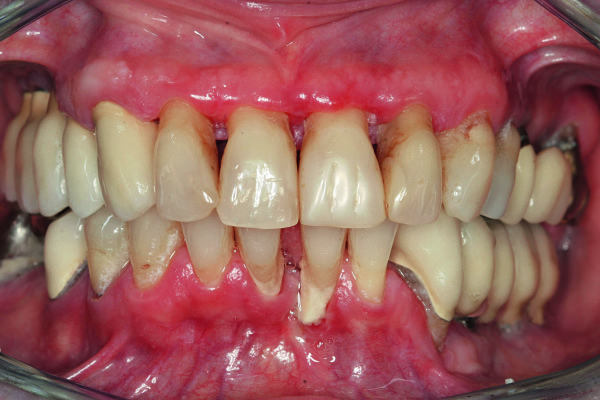

Parodontit, bütünlükdə parodont olaraq bilinən diş köklərini əhatə edən, dəstəkləyən və diş yuvasına fiksə edən xüsusi toxumaların, bağ aparatının və sümüyün iltihabıdır. Parodontit diş əti iltihabının gingivitdən sonrakı ikinci mərhələsi olub, gingivitdən fərqli olaraq müalicə edilmədiyində geri dönməyən degenerativ dəyişikliklərə, diş və onu əhatə edən sümük toxumasının itirilməsinə gətirib çıxara bilir. Parodontitin yaranma səbəbi bakterial plakdır. Lakin xəstəliyin inkişafında bir sıra yerli və ümumi faktorlar da rol oynaya bilir.

Parodontit tədricən dişətrafı sümük toxumasının itirilməsinə və bakterial plakın daha dərin təbəqələrə keçməsi ilə birlikdə ciddi dərinliklərə çatan sümük defektlərinin (və ya ciblərinin) yaranmasına gətirib çıxarır. Sümük toxumasının itkisi müəyyən bir zaman sonra dişlərdə ciddi hərəkətliliyin yaranmasına və qısa bir müddət sonra itirilməsinə gətirib çıxara bilir.

Parodontitin əsas əlamətləri bunlardır:

- Diş ətində şişkinlik və qızartı

- Diş ətində qanamağa meyllilik

- Dişlərin laxlaması

- Diş ətlərində çəkilmə